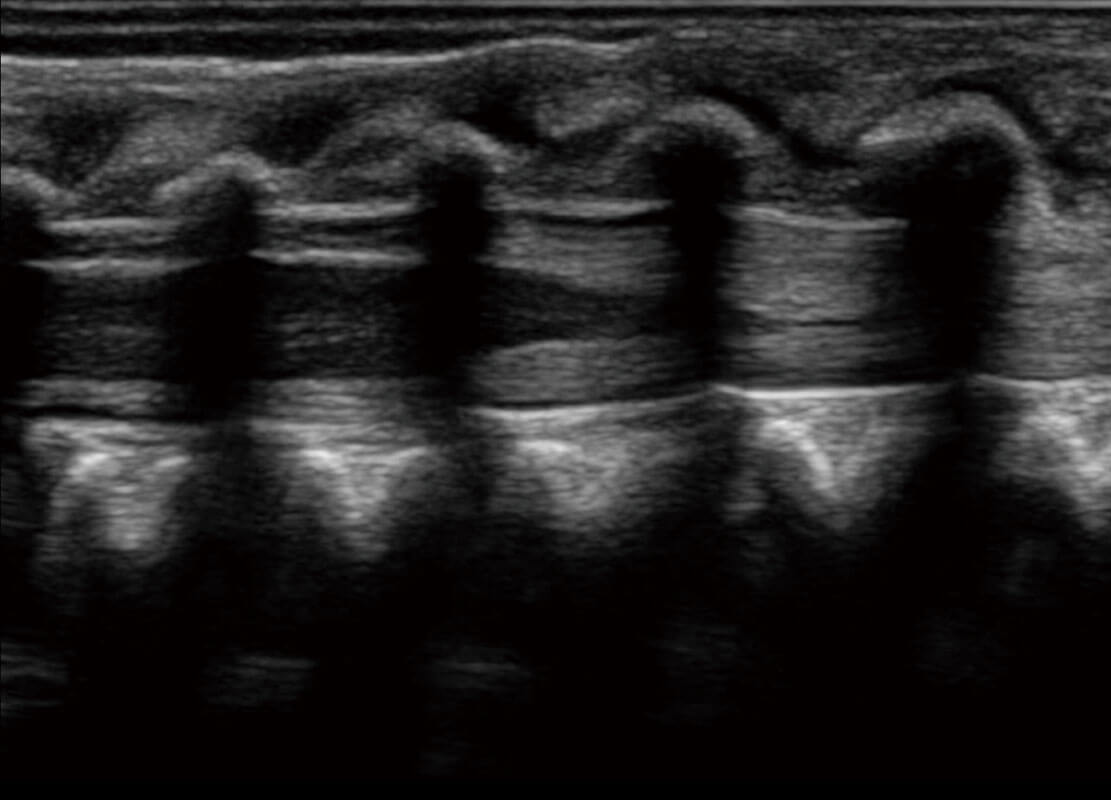

乳腺超声 / 新生儿

P60搭载宽频带线阵探头、宽景成像、弹性成像技术,为您提供乳腺应用方案。P60支持高频相控阵探头、线阵探头、腹部高频探头、腹部微凸探头等,丰富的探头群搭载敏感的彩色血流成像,适用于新生儿多种脏器检测要求,满足新生儿筛查需求。

• 乳腺导管癌

• 乳腺癌显微血流

• 新生儿肝血管癌

• 新生儿脊髓圆锥

• 新生儿心脏